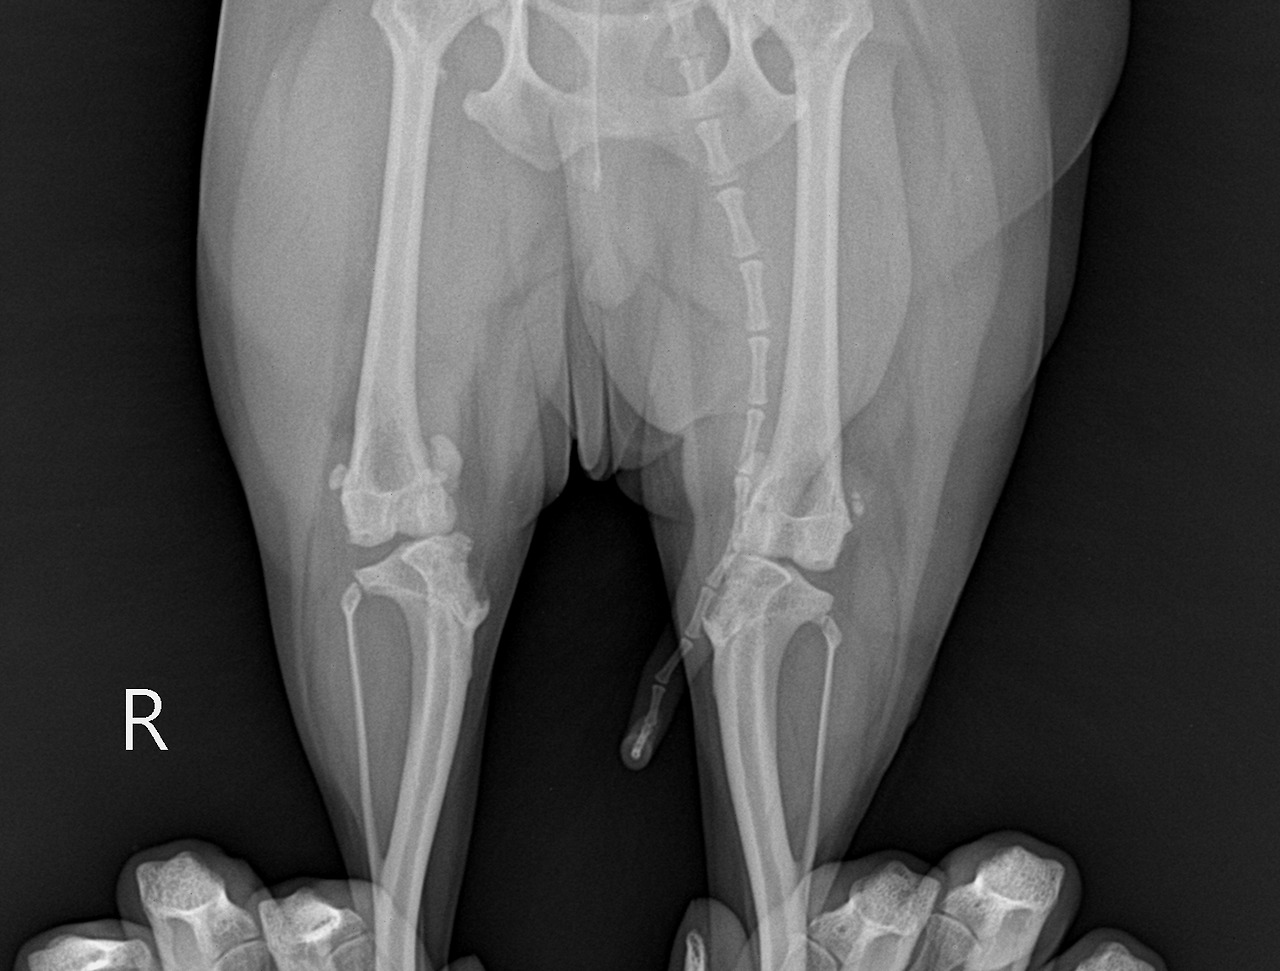

수술 전 찍은 코코 사진이다. 슬개골 탈구가 있는 사진이다.

우선 가까운 병원에 데리고 가서 엑스레이를 찍었다. 양쪽 다리를 다 찍었는데 슬개골 탈구가 맞고 심해지면 수술을 해야 한다고 했다. 바로 수술하기에는 당시 다리 상태가 그리 심각하지는 않았다. 그래도 마냥 내버려 둘 수는 없어서 다급하게 인터넷을 검색하고 강아지 관련 카페를 검색해 가입했다.

자세히 보면 뒷다리가 안쪽으로 휜 걸 알 수 있다.

우리가 해줄 수 있는 건 주기적으로 코코 다리를 살펴보는 것이었다. 그 와중에 안타까운 건 코코다리가 점점 안쪽으로 휘기 시작했다는 것이다. 뒤에서 보면 확연하게 티가 날 정도여서 지나가는 사람이 어쩌다 발견하면 말을 할 정도였다. 은근 그게 스트레스로 다가왔다. 누군가 자기 얘기를 하며 지적하는 걸 알아챈 똑똑한 코코가 예민해지는 걸 여러 번 보았다.